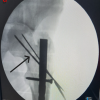

All patients were given spinal anesthesia (Sub-Arachnoid block), and the patient was positioned in a fracture table in the supine position, with the unaffected hip kept in an abducted position and the affected limb secured in a traction boot (Fig. 1a). The C-Arm was positioned in a way to change positions according to anteroposterior and lateral views. Closed reduction attempted under C Arm guidance. Once the status of reduction is achieved, the patient’s parts are painted and draped. If closed reduction was not achieved, we used a spike instrument through a small anterior incision to lift the proximal fragment (Fig. 1b). A 5 cm skin incision was made just above the tip of the greater trochanter. Subcutaneous tissue was dissected. The tensor fascia lata was cut. The gluteus medius was split along the line of fibers. The tip of the greater trochanter was identified. A bony entry was made using a cannulated bone awl at the tip of the greater trochanter (Fig. 1c). A guide wire was passed inside the cannulated bone awl, and the guide wire position was checked under C-arm guidance in anteroposterior and lateral views (Fig. 1d). Proximal reaming was done using a 16 mm reamer (Fig. 1e). Halifax nail was assembled and inserted and checked under C-arm guidance (Fig. 1f). A lateral cortex breaker was used to break the lateral cortex and used up to the neck level (Fig. 1g). The guide wire for a lag screw was passed at the center of the neck and head. Guide wire position was checked under C-arm guidance in both anteroposterior and lateral views (Fig. 1h). Reaming for lag screw was done (Fig. 1i). A lag screw of appropriate size was inserted up to the subchondral level. The lag screw was inserted in a way that 5 mm of its length was kept outside the lateral cortex (Fig. 1j). The set screw was applied from the top of the nail by a set screw introducer and fully tightened till it engages one of the grooves in the lag screw to prevent the “Z” and reverse “Z” effect. Moreover, the introducer was left along with the set screw. The tri-wire of size 5 mm, shorter than the lag screw, was inserted till it engages in the sub-chondral bone, and the position was checked under C-arm guidance (Fig. 1k). Now, using the set screw introducer, the fully tightened set screw was released 1/4th turn. This is to maximize the micro movements between the fracture fragments. The introducer was removed now. End cap was applied in the lateral end of the lag screw in a way to cover the outer prominence of tri-wire, to prevent the tri-wire pull out (Fig. 1l). Distal locking was applied mostly in the dynamic position using the sleeve (Fig. 1m). A head cap was applied over the top of the nail after removing the Jig to prevent bony overgrowth inside the nail top (Fig. 1n). Final position of nail was checked under C-arm guidance in both anteroposterior and lateral views (Fig. 1o). A thorough wound wash was given, and the wound was closed in layers. A sterile dressing was applied.

Figure 1: Intraoperative picture and Halifax nail instrumentation.